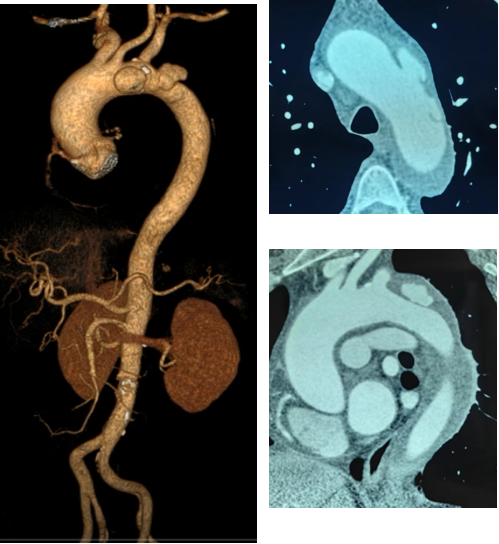

韩某,男,53岁,“查体发现主动脉弓部溃疡15天”入院,主动脉CTA提示:主动脉溃疡(弓部);2. 主动脉壁内血肿。患者高血压病史8年,最高210/130mmHg,无规律服药。

术前 CTA

术前造影

术前

术后

手术用时115分钟